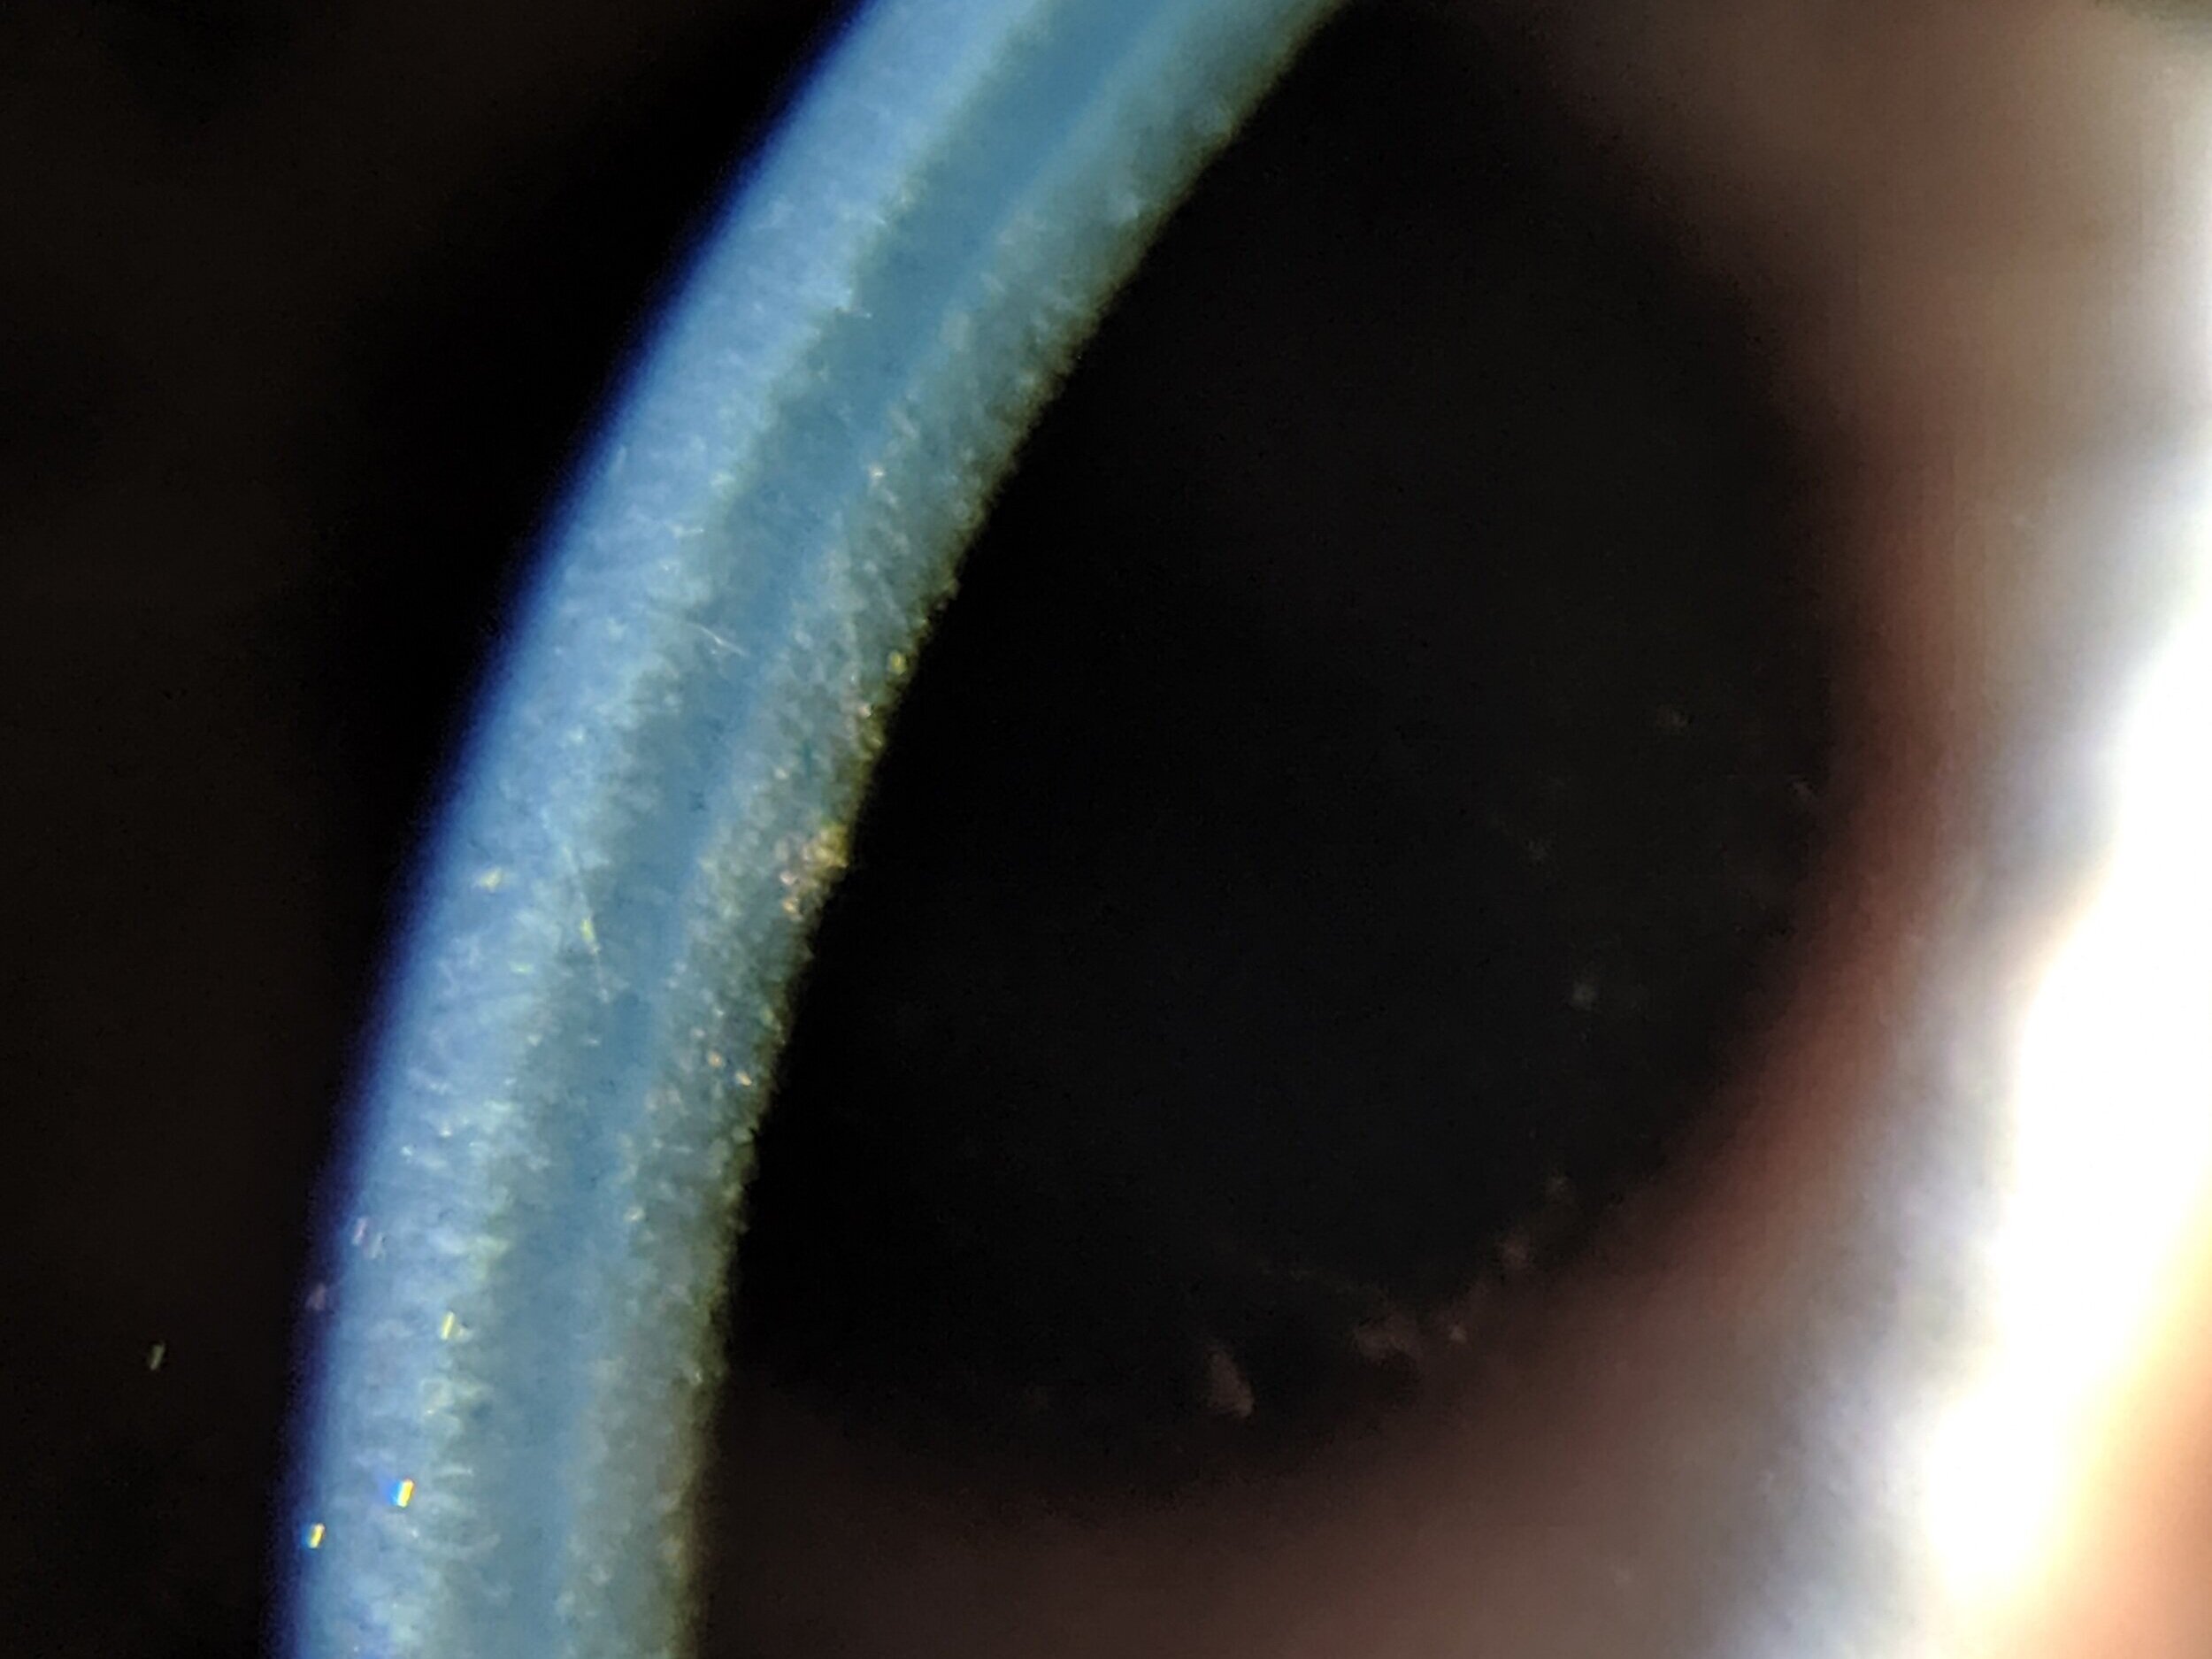

1단계 구타타 (guttata) 단계에서는, 구타타만 관찰됩니다.

구타타는 gutta, guttae, 라틴어 방울에서 나온 용어로서,

각막 내피에 인접한 데스메막에 세포 분비 물질이 쌓이거나 혹처럼 튀어나오는 부분이 생기는데,

이렇게 일부분이 두꺼워지면서 사마귀 같은것들이 튀어나온것이 꼭 물방울 같은 모양처럼 보이게되는데

이를 구타, gutta라고 하며, 복수 용어가 gattae 가 됩니다.

이때 Guttata 구타타라는 용어는 Vogt 에의해서 처름 사용된 용어로 물방울을 닮았다고하여,

이름 붙여진 용어입니다.

이때는 세극등 검사에서 구타타가 관찰되며, 이때는 아직까지 증상이 없는 시기고,

시력 및 각막 두께는 정상입니다.

이처럼 구타타는 관찰되나, 각막 부종은 없는 상태를 Endothelial dystrophy 라고 용어합니다.